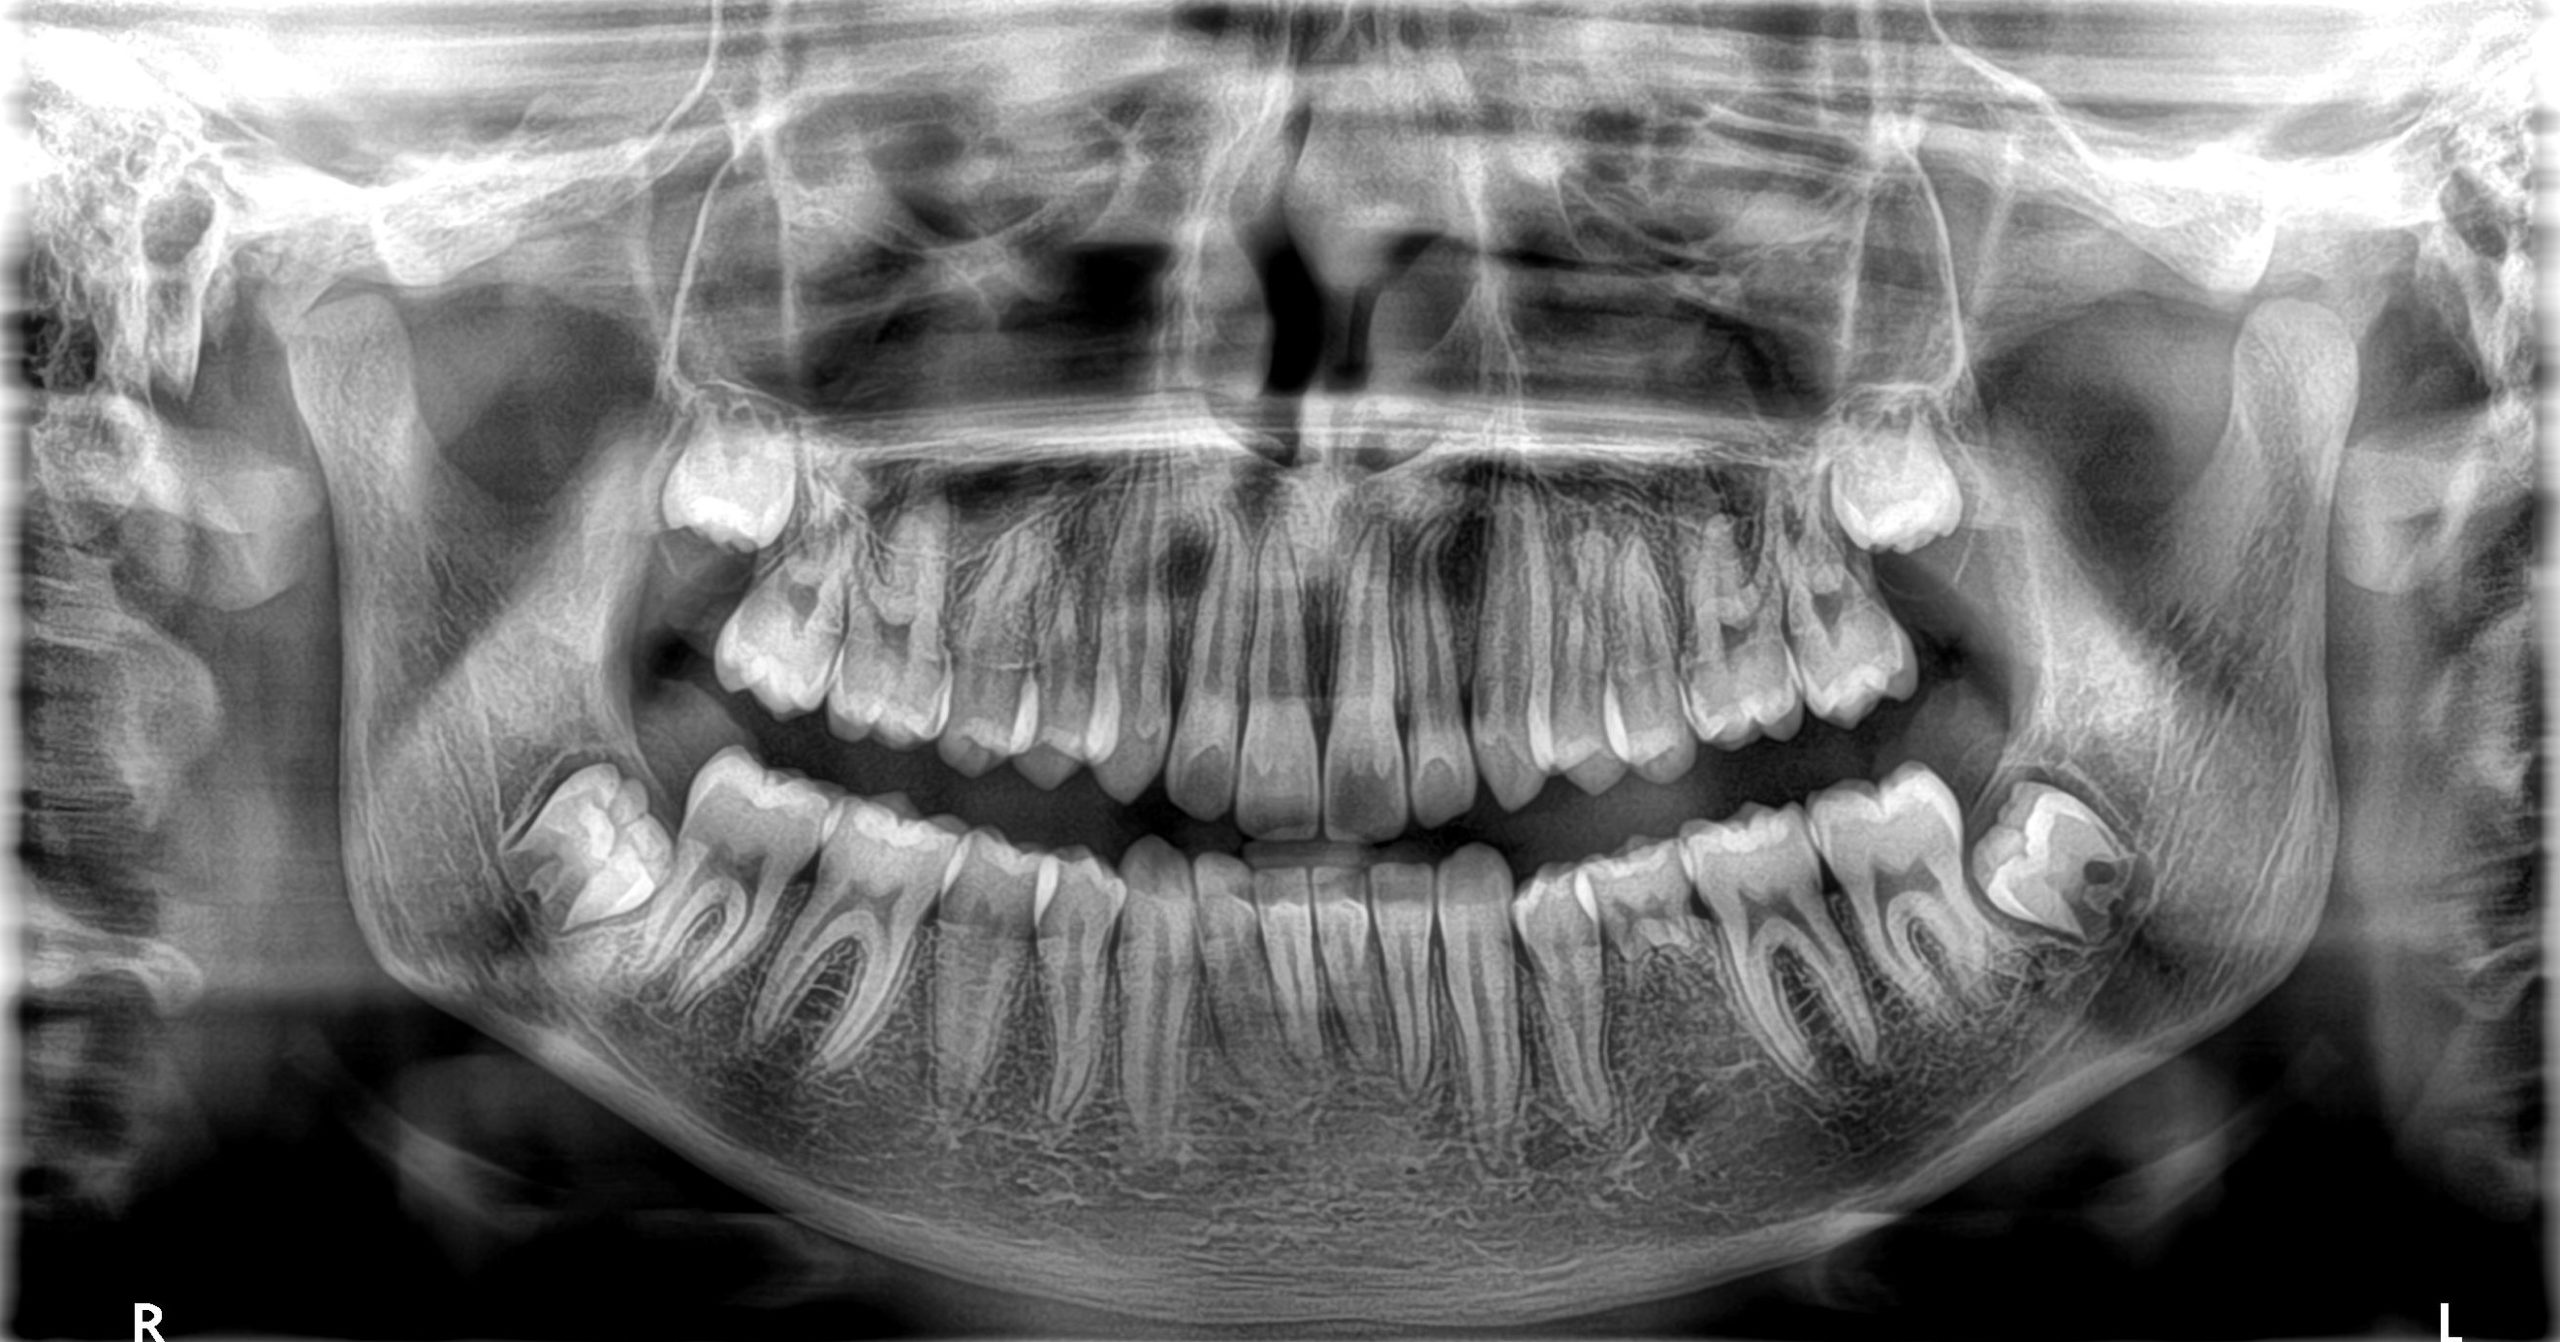

Pametne inovacije potiču preciznost na svakom pregledu

Kristalno jasne slike s ograničenim artefaktima i šumom

Najširi raspon veličina volumena s do 14 vidnih polja